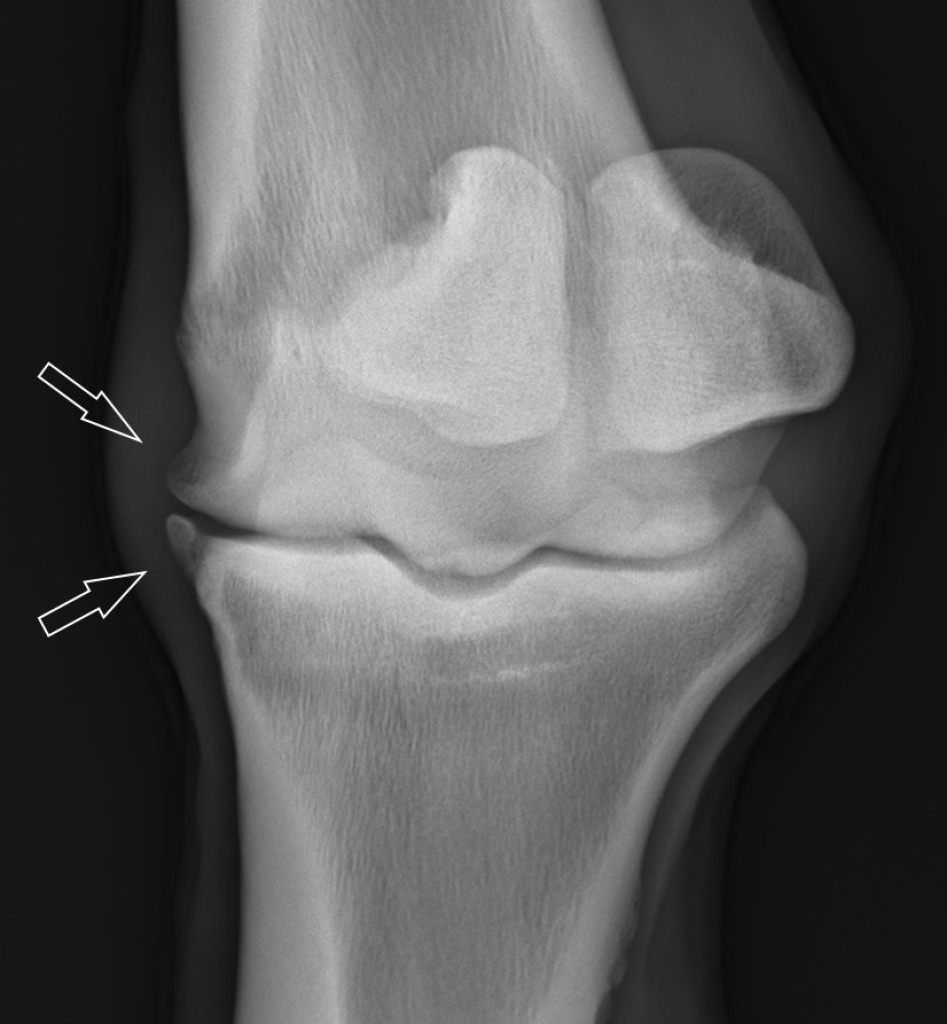

Kogelgewricht met forse haakvorming aan de rand van het gewricht als gevolg van artrose.

Verschil tussen een gezond gewricht en een gewricht met artrose.